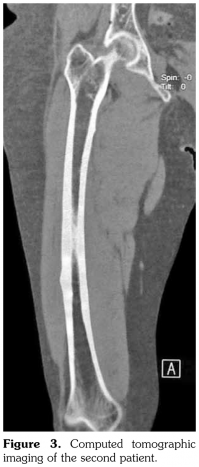

Case 1– A 73-year-old female patient presented with low back, knee, and anterior thigh pain. Pain severity was 8 over 10 point according to visual analog scale. She had difficulty in walking because of pain. She had a history of arthroscopic knee surgery for meniscal pathology in her left knee five years ago. She had chronic low back pain due to L4-5 disc herniation and lumbar spinal stenosis. She had been treated for osteoporosis with alendronate for two years, then with salmon calcitonin for two years and ibandronic acid for a year. Neurological examination was normal. Plain radiographs revealed bilateral lateral cortical thickening in the femur (Figure 1). Magnetic resonance imaging was done to rule out fracture. Bone scintigraphy showed increased uptake in bilateral femoral diaphysis. Routine biochemical tests were normal except increased urinary deoxypyridinoline. Urinary deoxypyridinoline level was 63 nM/mMCre (normal range: 3-7.4 nM/mMCre).